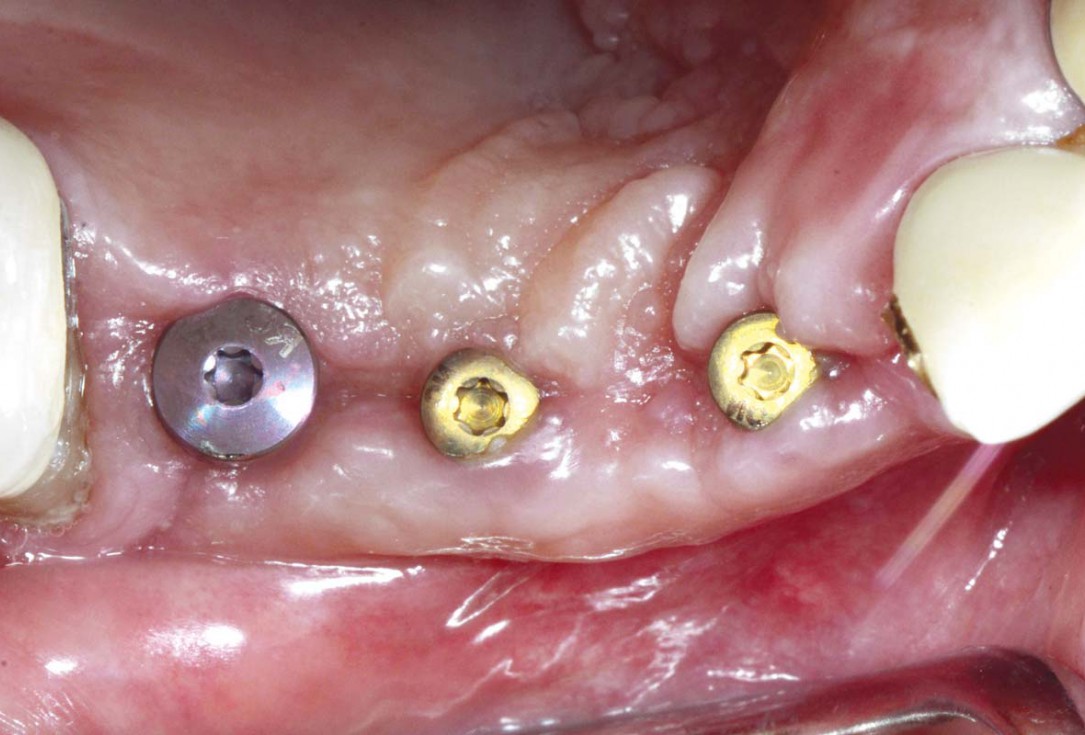

Preoperative situation – Maxillary defect in area 14-16 (loss of implant 16 due to periimplantitis, tooth 14 extracted recently and area 15 already edentulous for a while)